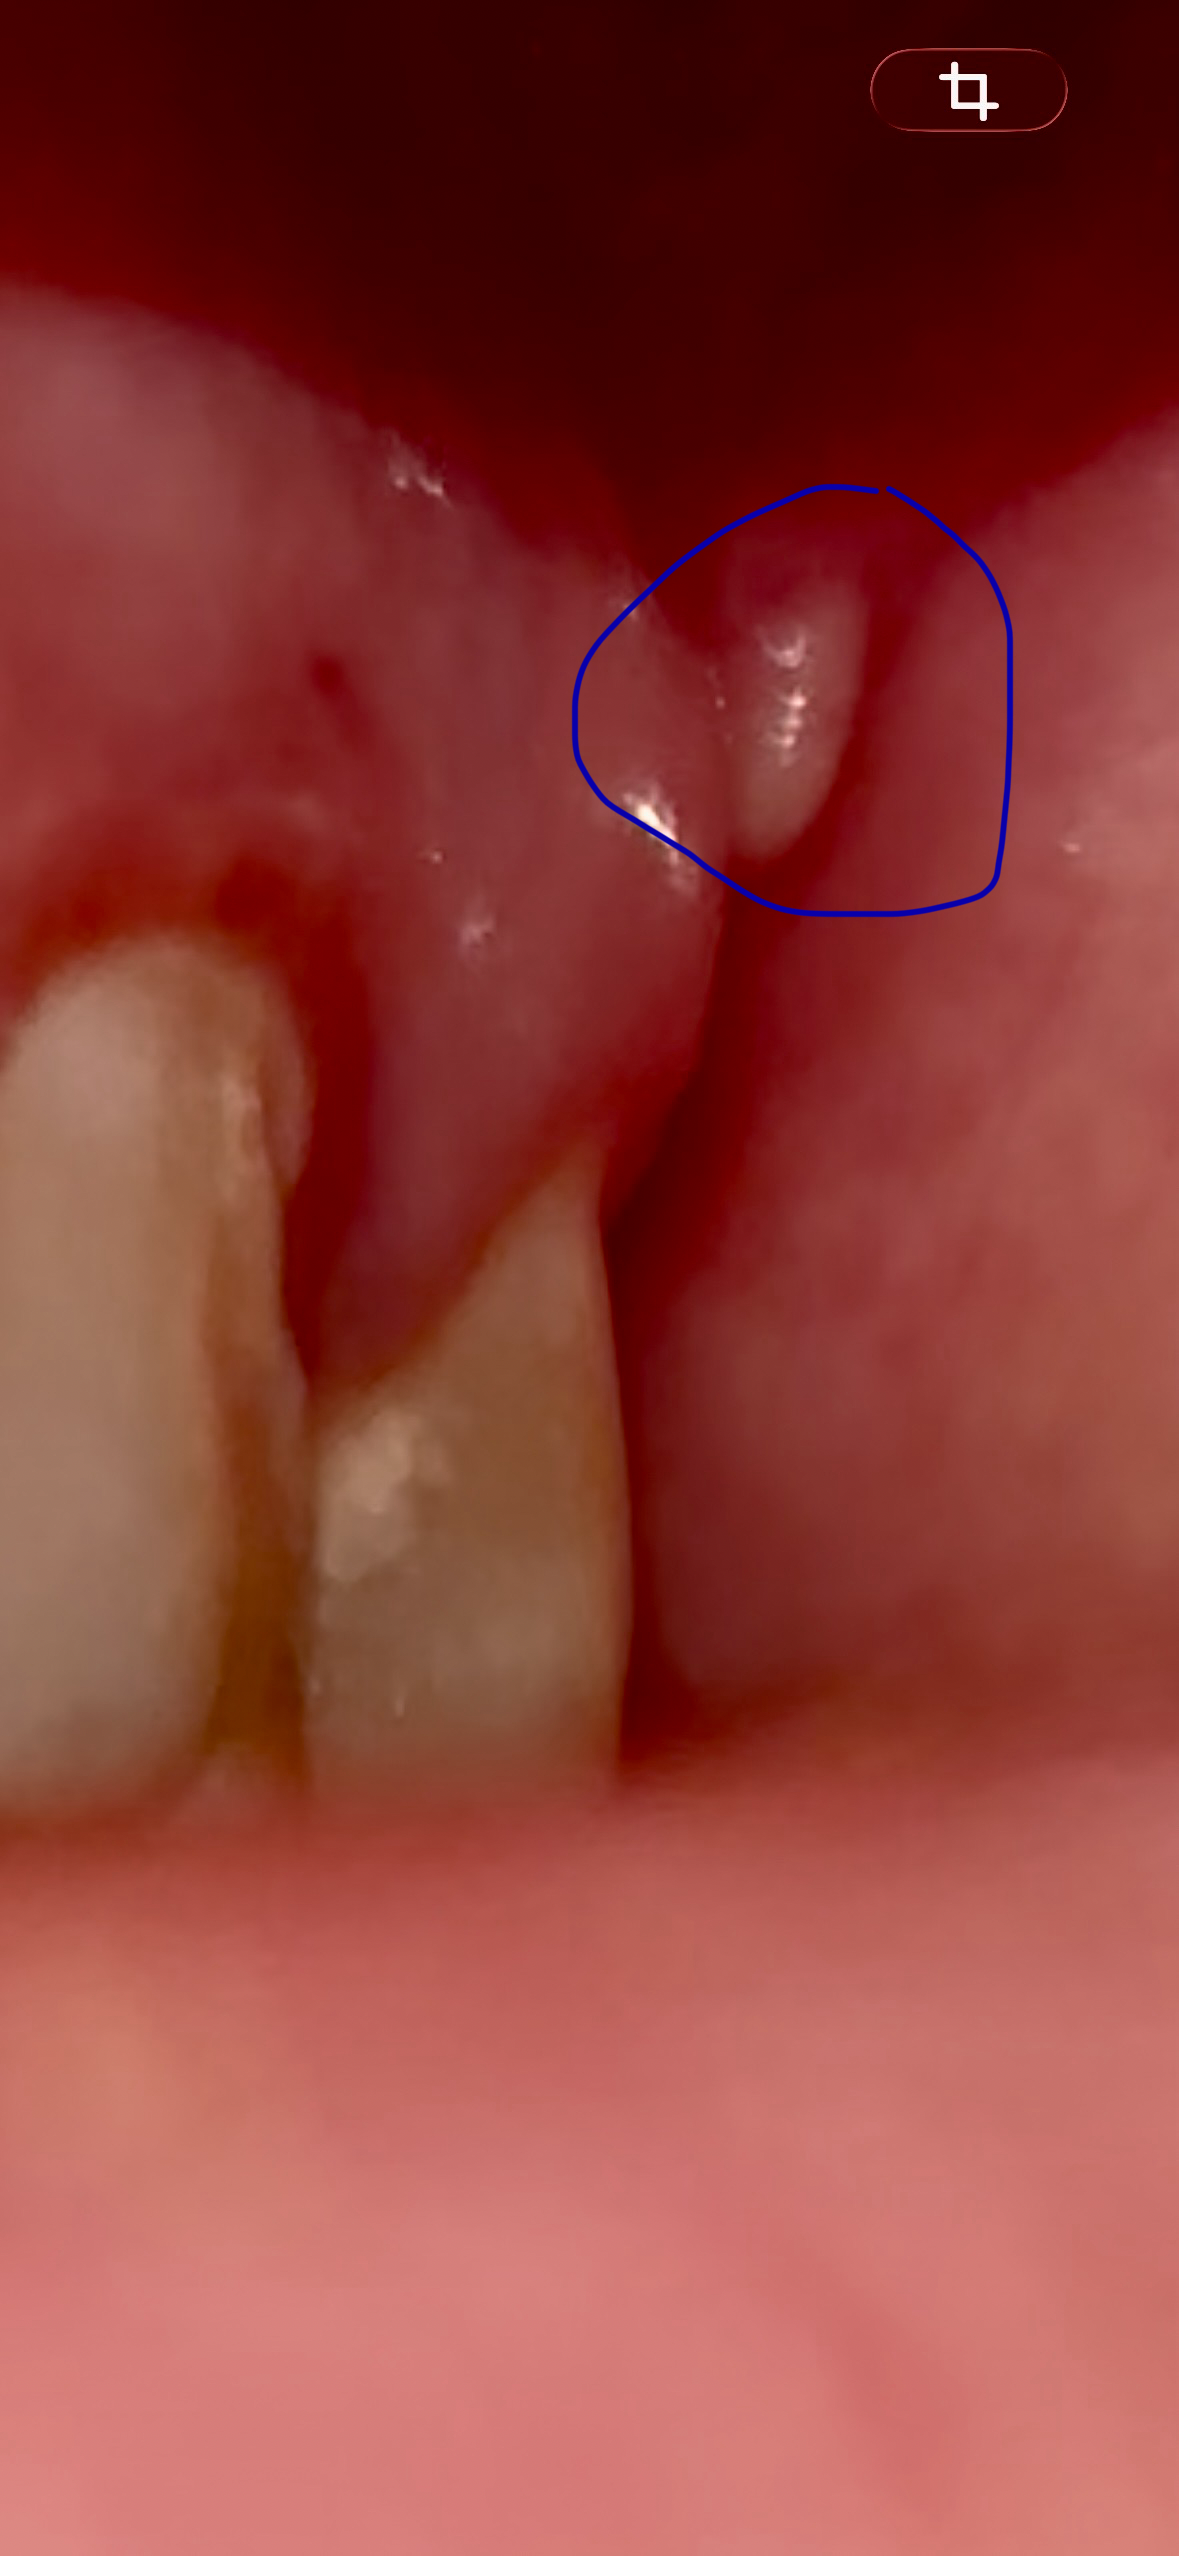

Добрый, день беспокоит такая проблема вот уже 3 день как на верхней челюсти на десне с лева между 7 зубом и там где должен быть 8 зуб. Но его у меня нету с лева еще не вылез а вот с права есть. В сентябре лечил зубы 5 и 6 делали кт верхней челюсти врач говорил что повезло что зубы мудрости ровно растут. Вообщем касательно симптомов то есть такое как не чувство давление а больше точечная боль, когда задеваю то место щекой или если левую часть лица напрягаю. По внешнему виду, оно что ли белое и свисает. А на ощуп выпуклость что ли.